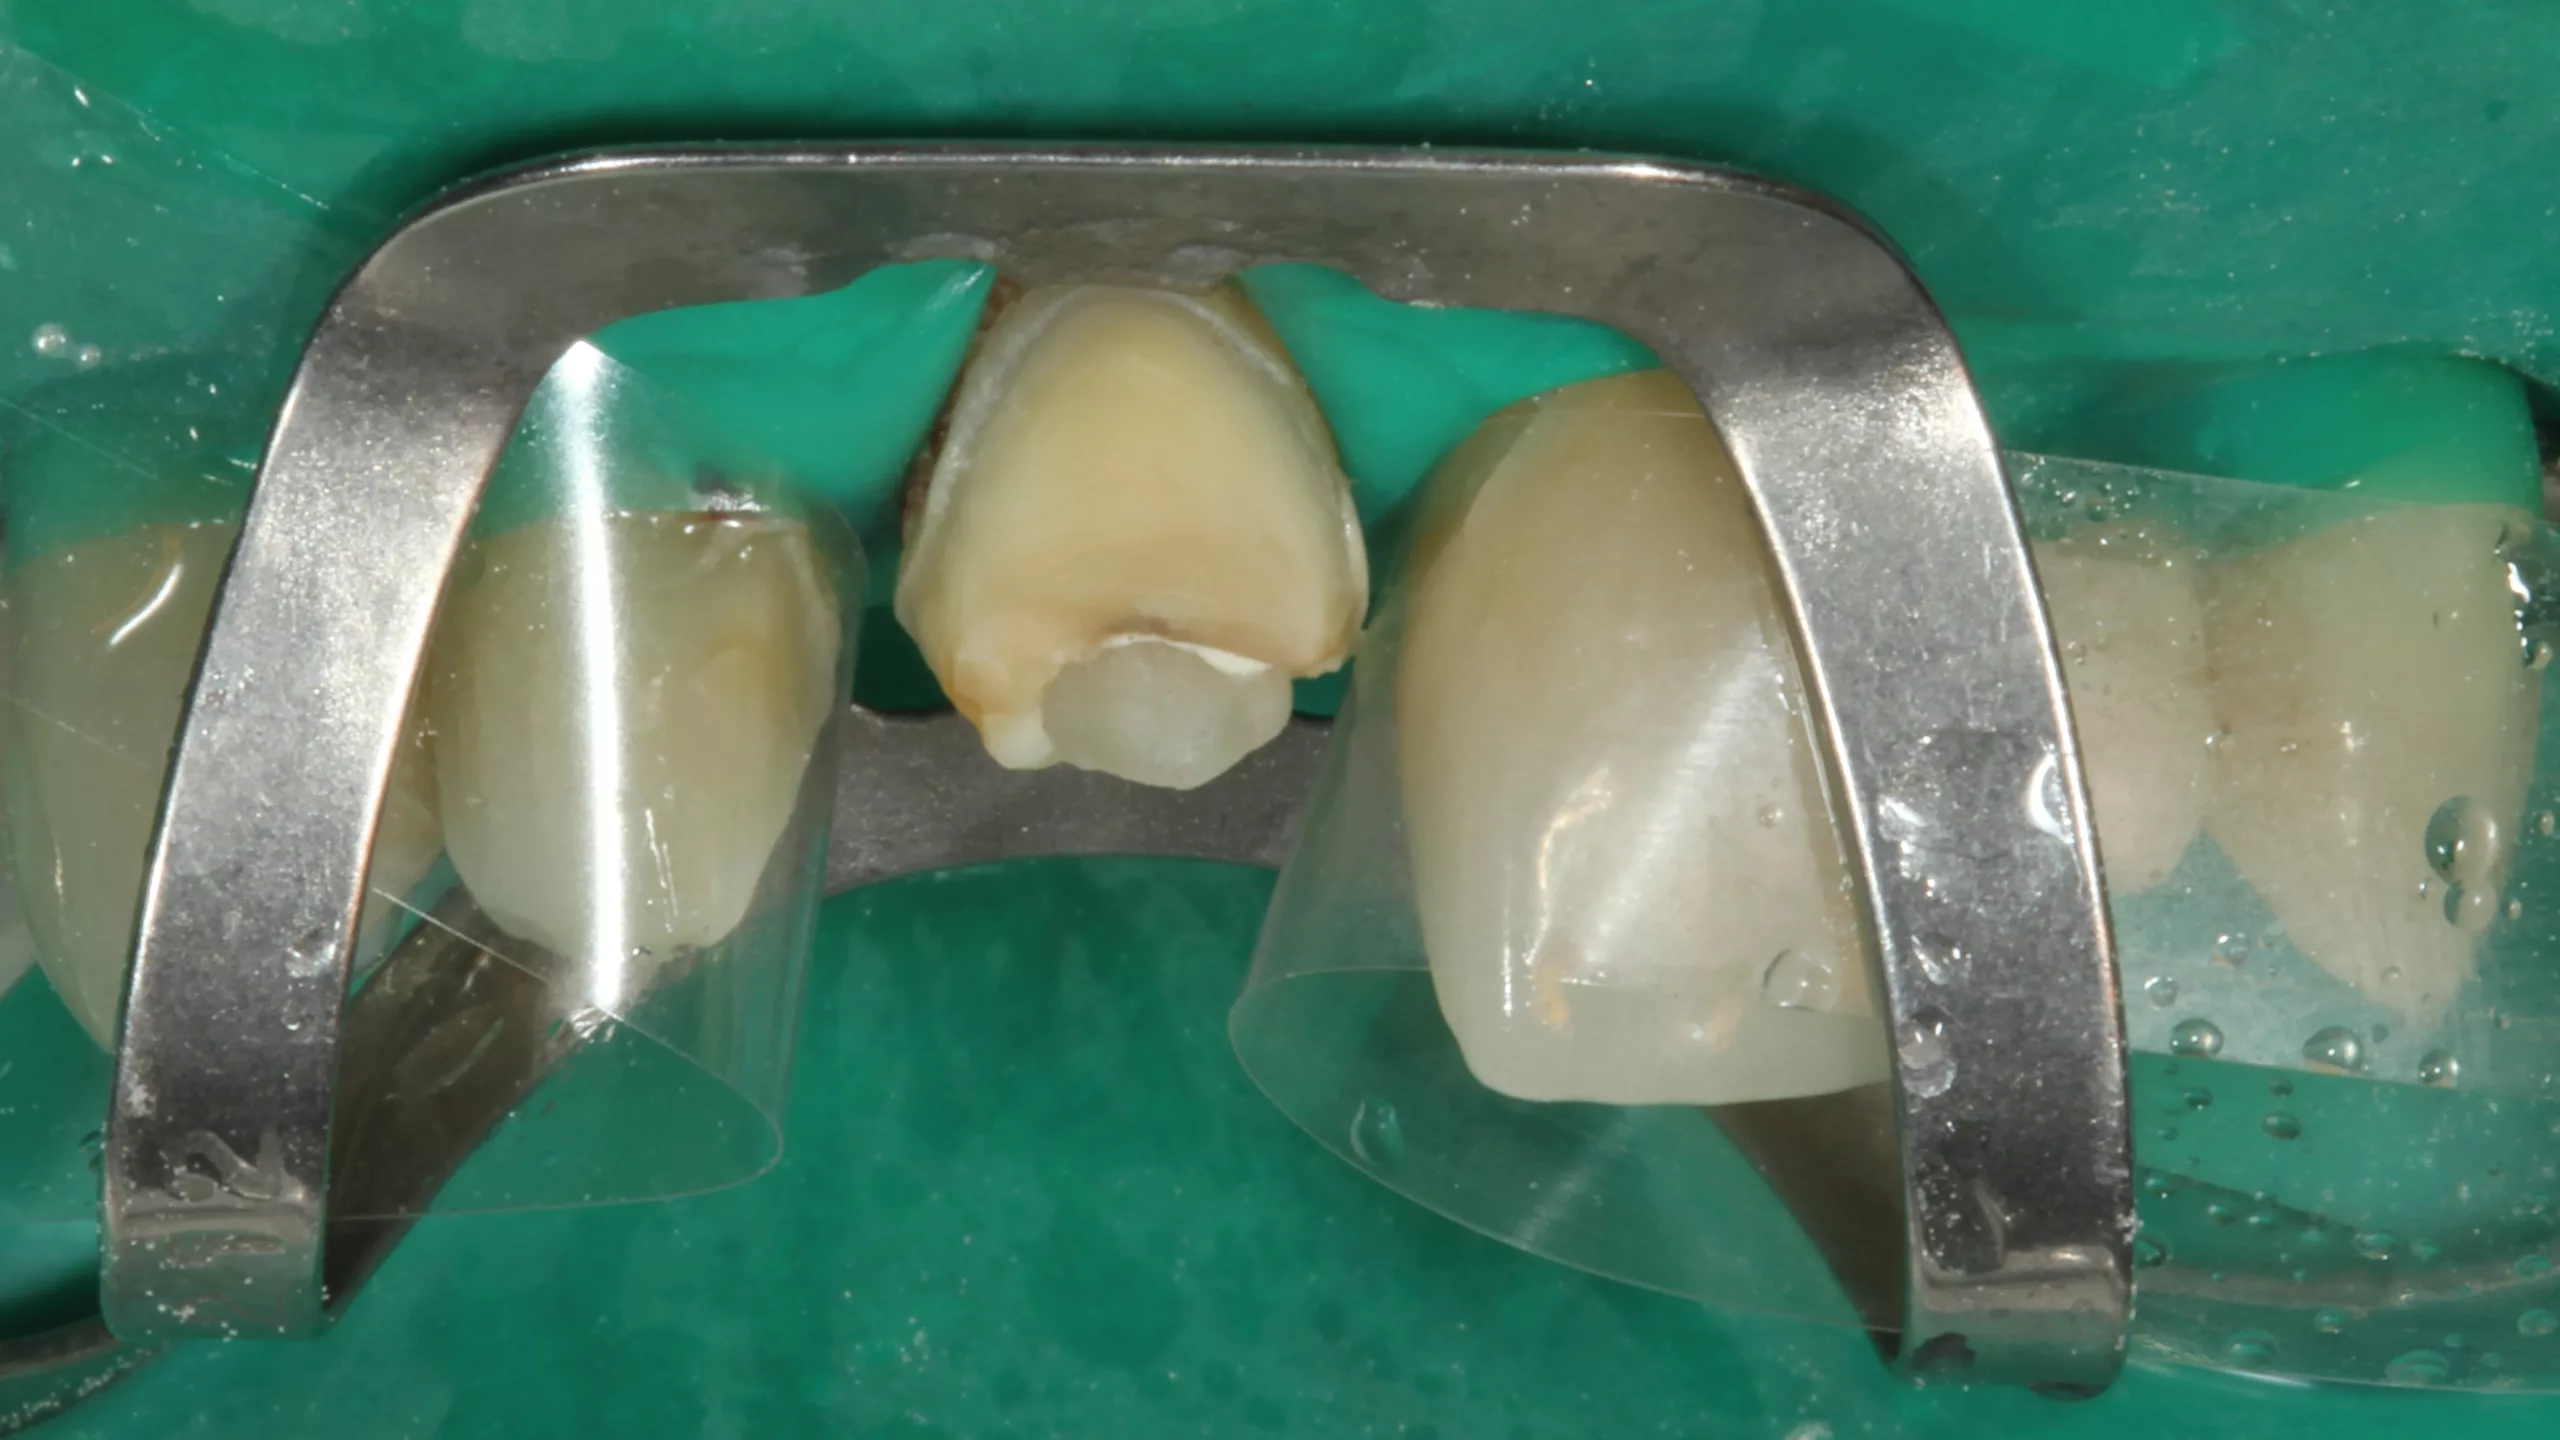

Bedingt durch einen Unfall während der Tragezeit des Provisoriums brach das Provisorium an Zahn 11 im inzisalen Drittel samt dem darunter befindlichen, postendodontologischen Kompositaufbau ab. In der Abbildung 33, die die Situation bereits bei der Vorbereitung zur adhäsiven Eingliederung der Gesamtarbeit zeigt, ist der enorme inzisale Substanzverlust gut erkennbar: Erkennbar sind ebenfalls noch Reste des als Aufbaumaterial verwendeten Bulk-Flow-Komposits SDR Flow+ (Dentsply Sirona) in der Farbe U sowie etwas weiß-opaken Venus Diamond Flow Baserliners (Kulzer). Glücklicherweise war der Präparationsrand intakt; die Laborarbeit passte perfekt. Ein Problem bestand nun in der Auswahl des Befestigungsmaterials: Im Prinzip mussten hier gleichzeitig ein Stumpfaufbau und eine adhäsive Befestigung bewerkstelligt werden. Da alle herkömmlichen adhäsiven Befestigungsmaterialien nicht für die Indikation Stumpfaufbau freigegeben sind, schied diese große Gruppe an Befestigungsmaterialien aus. Die Befestigung mit einem adhäsiven Stumpfaufbaumaterial in Form eines „Post & Core“-Konzeptes wäre ein schlechter Kompromiss, da diese Materialien aufgrund ihrer schlechten Polierbarkeit normalerweise nicht dem direkten Kontakt zum Mundmilieu ausgesetzt werden sollten: Erhöhte Plaqueanlagerung oder sogar Verfärbungen am Fügespalt wären ein Risiko, das man ungern eingehen würde.

Das einzige Material, das in diesem Fall gemäß den Vorgaben des Herstellers zur Anwendung infrage kommen würde, war erneut Visalys CemCore, da dieses Material sowohl für die adhäsive Befestigung als auch für einen adhäsiven Stumpfaufbau freigegeben ist. Der Zahnstumpf des Zahnes 11 wurde zusammen mit dem noch verbliebenen Aufbaukomposit mit 50 ?m Al2O3 intraoral abgestrahlt (Rondoflex, Kavo). Die Nachbarzähne wurden mit 2 Frasacostreifen geschützt (Abb. 33). Im Anschluss erfolgte eine Schmelzätzung mit Phosphorsäuregel und erneut die Applikation des Visalys Tooth Primers – exakt nach Herstellerangaben. Die Vorbehandlung der bereits im Labor mit 50 ?m Al2O3 abgestrahlten Zirkonoxidkrone geschah äquivalent zum vorangegangenen Fall: Fixierung an einem Pinselhalter mit Clip, Desinfektion, farbliche Markierung der Klebefläche mit einem Permanentmarker, Abstrahlen mit Cojet, Applikation, Einwirken und Verblasen des Visalys Restorative Primers. Die Abbildung 34 zeigt die Polymerisation von Visalys CemCore (ebenfalls in der Farbe Universal [A2/A3]) nach vollständiger Überschussentfernung der Kleberreste. Da es Sinn macht, bei der Befestigung von Frontzahnrestaurationen in einer Sitzung dasselbe Befestigungssystem zu verwenden, um keine ästhetischen Beeinträchtigungen durch unterschiedliche Farben oder Opazitäten zu riskieren, wurden die anderen 3 adhäsiven Teilkronen ebenfalls mit Visalys CemCore befestigt – allerdings jeweils einzeln, da die Kofferdamklammer nur jeweils eine Einfassung und Erreichbarkeit eines einzigen Zahnes erlaubt.